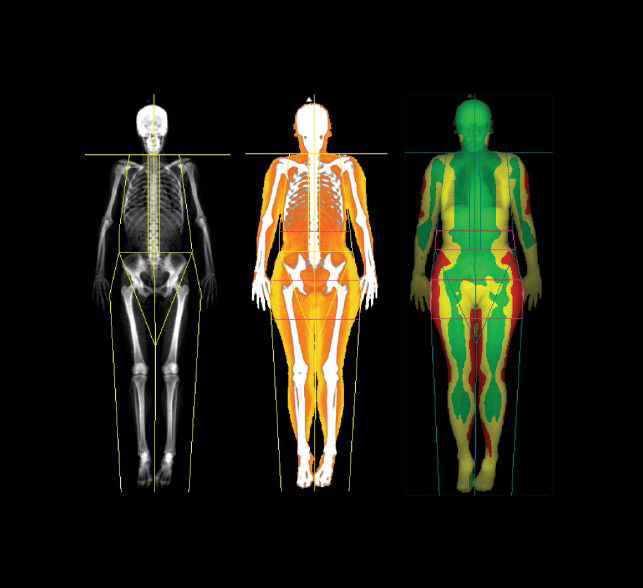

1. Color Mapping available on Lunar iDXA only.